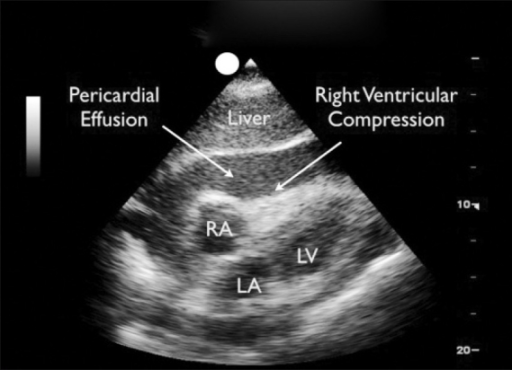

Subcostal view

The subcostal view can also be difficult to obtain. In the FAST scan, visualisation of the chambers of the heart is less important; the primary aim is assessment of the pericardial space.

Note the obliteration of the right ventricle. Goodman A, et al. - CC-BY-SA 3.0 Link